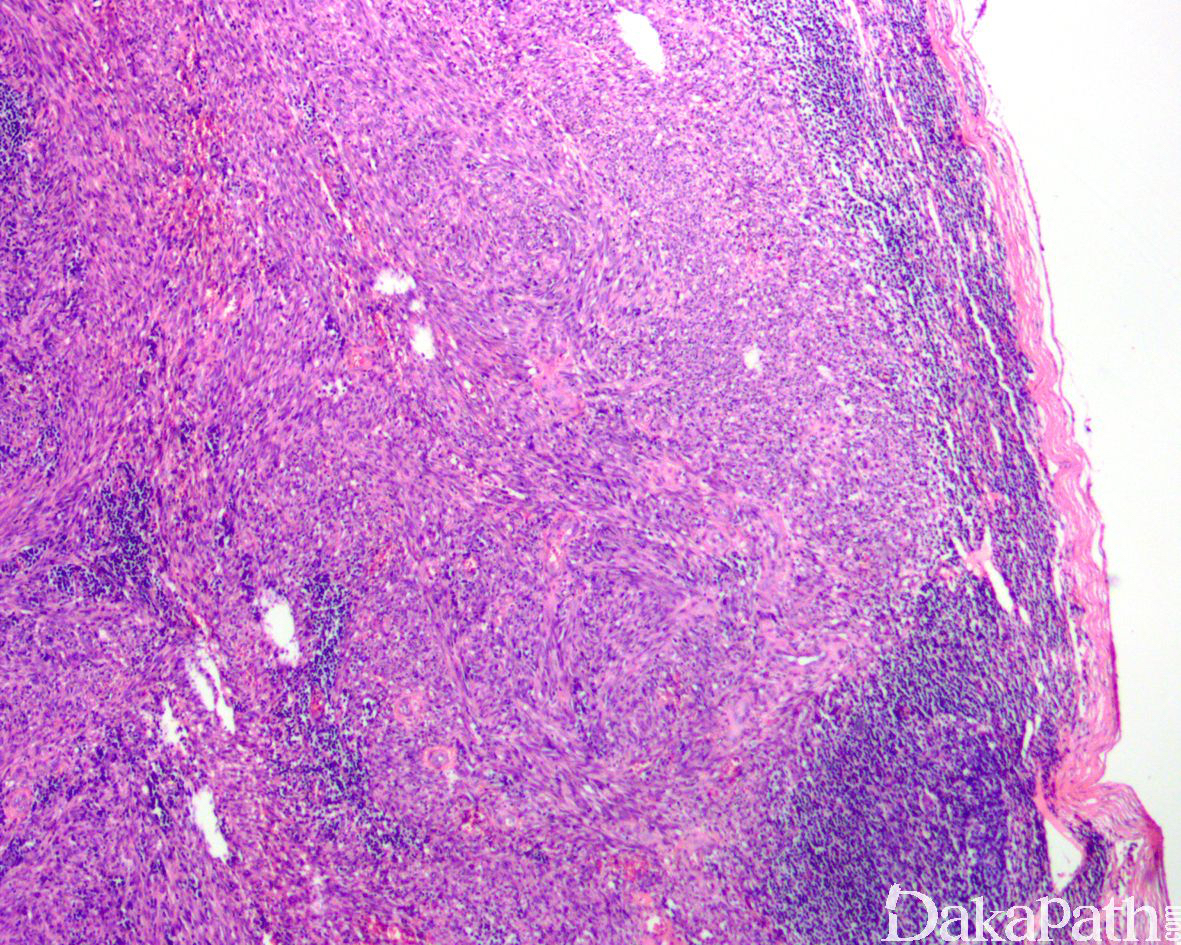

典型的卡波西肉瘤细胞无明显的异型性,核分裂像也不多见,但少数病例中瘤细胞分化较差,异型性明显,可见较多的核分裂像。依据病变进展分为四期:

IV 期为结节期:结节期的病变边界清楚,主要由网状或裂隙状的毛细血管及其周围纵横交错的嗜酸性梭形细胞组成,梭形细胞有一定异型性,核分裂偶见;梭形细胞和血管之间为含有红细胞的裂隙,横切面呈筛孔状或蜂窝状,在梭形细胞内或细胞外可见抗淀粉酶消化 PAS 阳性的嗜伊红色透明小体,结节的边缘常见炎症细胞浸润、含铁血黄素沉着和扩张的血管。 典型的卡波西肉瘤细胞无明显的异型性,核分裂像也不多见,但少数病例中瘤细胞分化较差,异型性明显,可见较多的核分裂像。